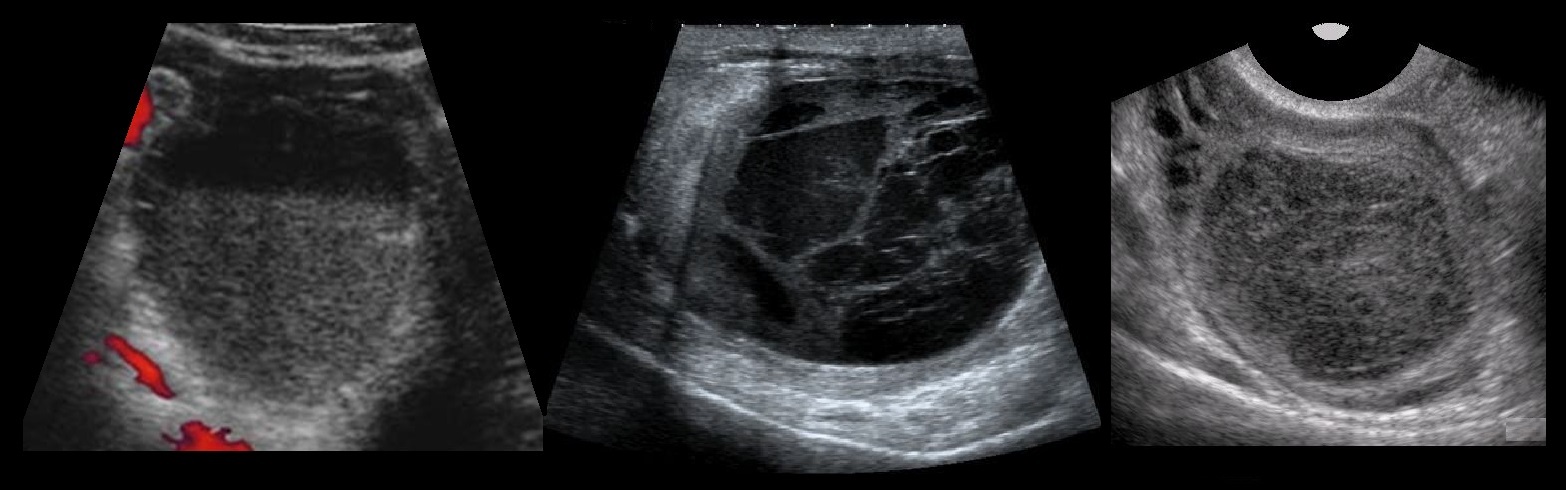

КТ диагностика тубоовариального абсцесса: Подходы и изображения

Раздел: Объективный взгляд